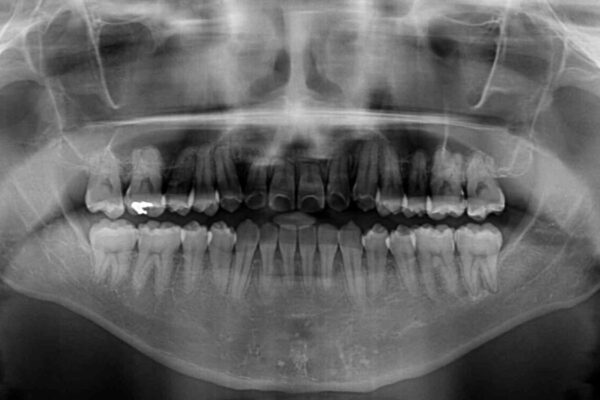

治療前

• 左右の八重歯が気になる ワイヤー装置での咬み合わせ改善 治療前画像